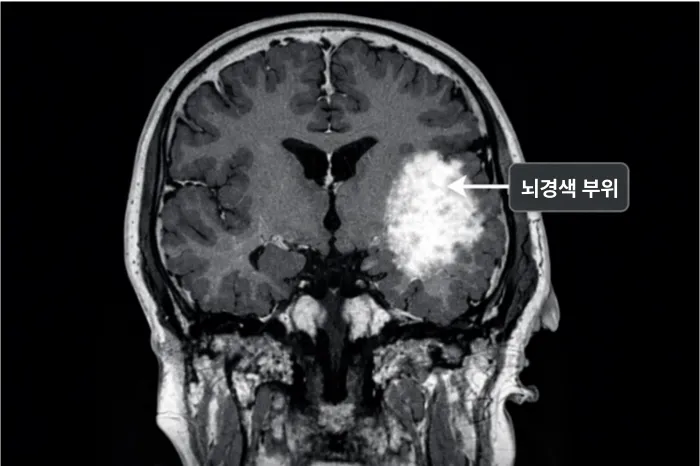

뇌경색이란 뇌로 가는 혈류가 막혀 뇌세포가 손상되는 상태를 말합니다.혈류가 차단되면 해당 부위의 뇌 조직이 기능을 잃게 되는데, 이로 인해 다양한 증상이 나타납니다. 조기에 발견하고 치료하면 상당 부분 회복이 가능하지만, 놓치면 영구적인 장애가 남을 수도 있습니다. 초기 증상을 정확히 알고 빠르게 대처하는 것이 무엇보다 중요합니다.